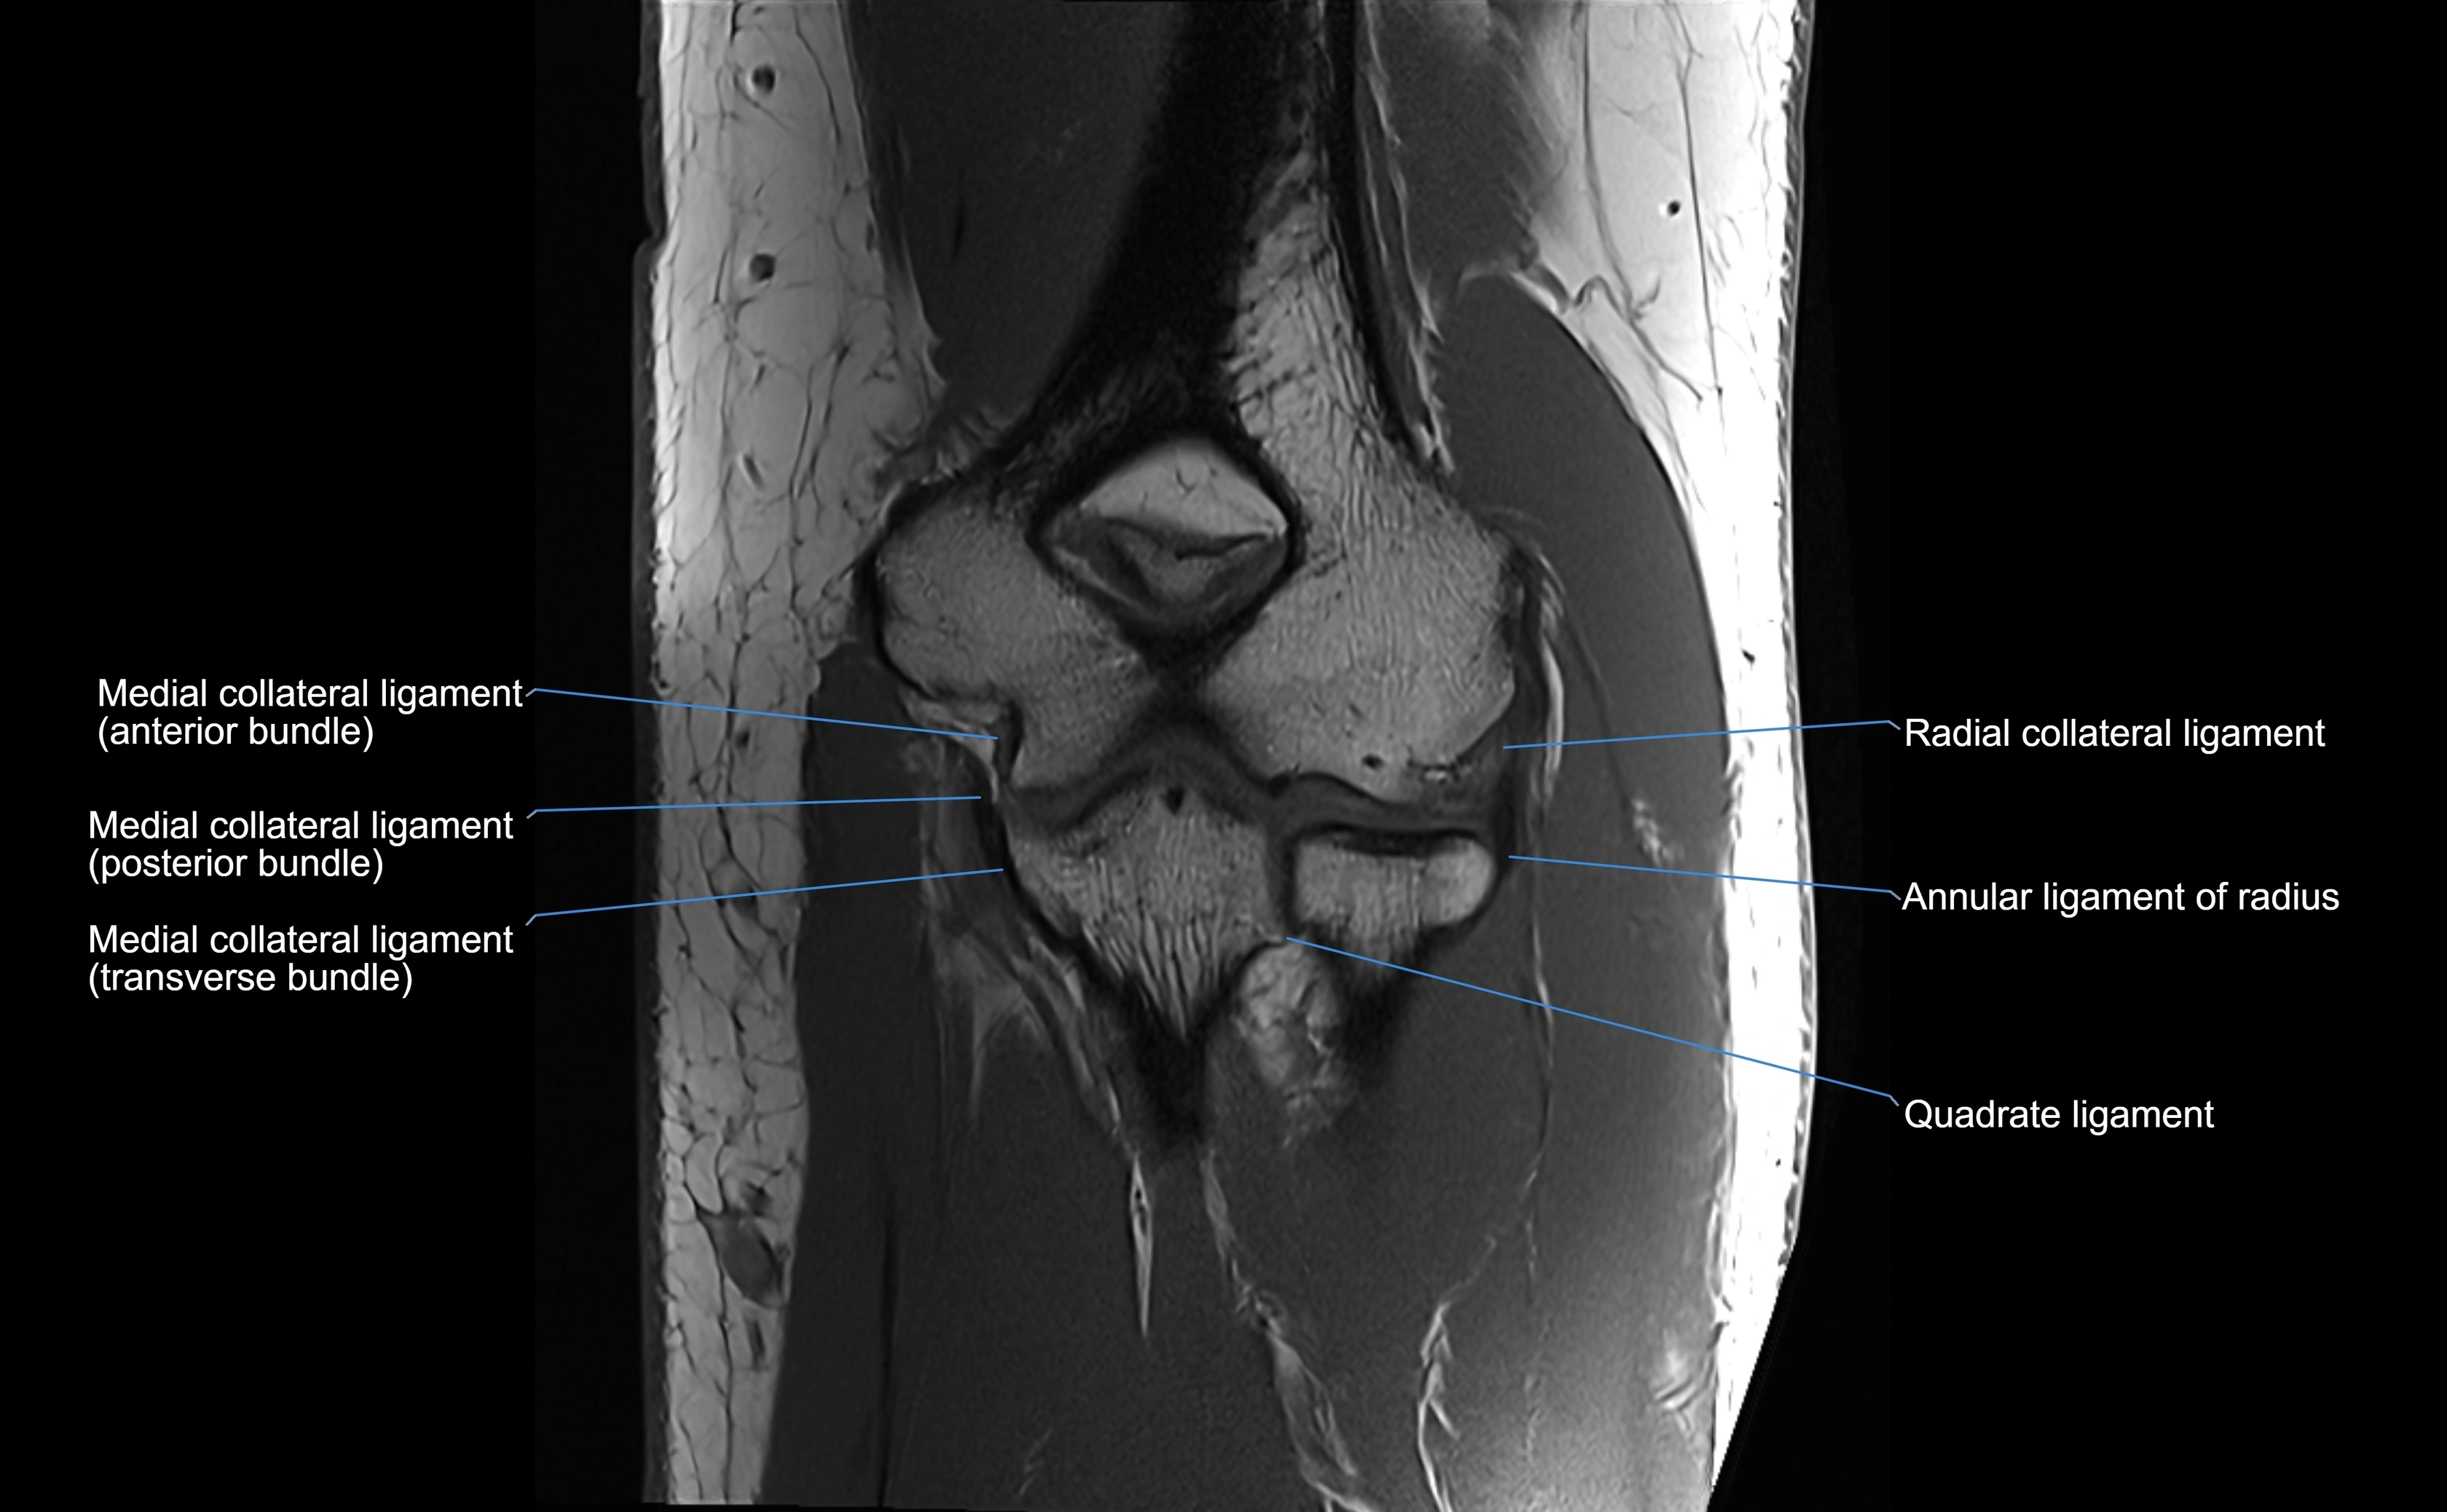

Origin, Course, and Insertion

• Origin: Arises from the anterior margin of the radial notch of the ulna.

• Course: Forms a strong circular band that wraps around the radial head and neck, maintaining them within the radial notch.

• Insertion: Attaches to the posterior margin of the radial notch, completing a fibrous ring around the radial head.

Relations

• Superiorly: Blends with the capsule of the elbow joint.

• Inferiorly: Supported by the quadrate ligament at the neck of the radius.

• Medially: Attached to the ulnar radial notch.

• Laterally: In contact with the radial head and its articular cartilage.

• Anteriorly: Related to the radial collateral ligament of the elbow.

• Posteriorly: Continuous with the elbow joint capsule.